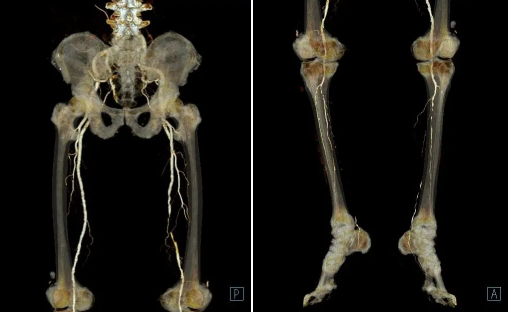

VR 获取的是复杂解剖结构的空间三维关系,可以同时显示受检部位的表面及深部结构。故对于下肢动脉的整体走形分布、侧支循环、血管畸形等有重要价值,还可以提供血管与骨骼之间的空间关系,方便临床进行手术定位。

案例二

患者男、70岁,行双下肢CTA后诊断为:双下肢动脉粥样硬化表现,右侧股动脉中段节段性管腔闭塞,双侧髂总动脉、双侧髂内外动脉局部中度-重度狭窄,余双下肢部分动脉微-轻度狭窄。(供稿:CI室)